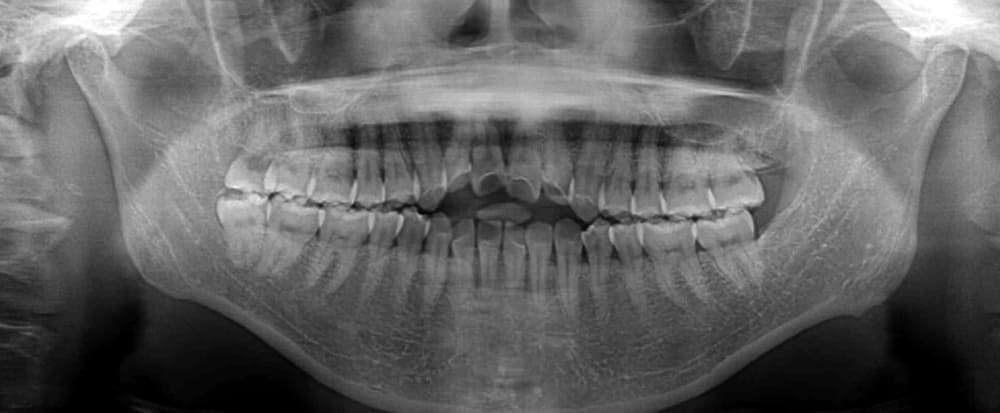

パノラマ写真では、上下顎右側に親知らず(智歯・8番)が確認されました。

この親知らずが開咬の原因の一部である可能性が高いため(親知らずが他の歯を圧迫した結果、開咬になっている可能性がある)、治療開始と同時に抜歯を行いました。

治療期間はおよそ2年で、術後のパノラマ写真では、歯根吸収もなく、良好な位置関係で歯列が安定しています。